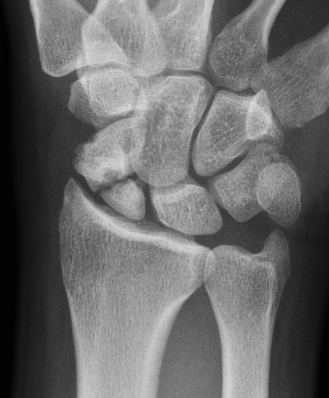

Nonunion with minimal displacement and minimal resorption

Nonunion with significant displacement and bone resorption

Proximal pole fracture with displacement and absorption